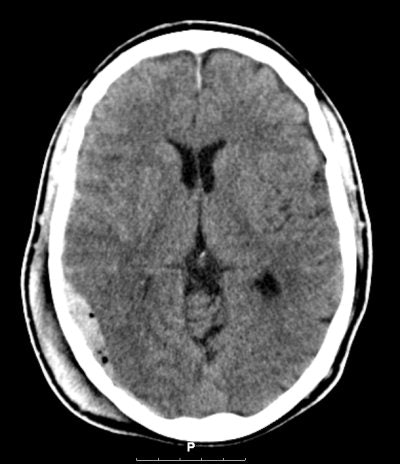

![]() |

| Routine CT scanning may still be the best option for patients with minor head injury. Image courtesy of Dr. Marion Smits. |

If the sensitivity of selective strategies falls to less than 91%, which is quite feasible given that more than 90% of MHI patient CT scans are "normal" (i.e., show no signs of traumatic abnormality), routine CT scanning becomes the clear dominant strategy, she said.